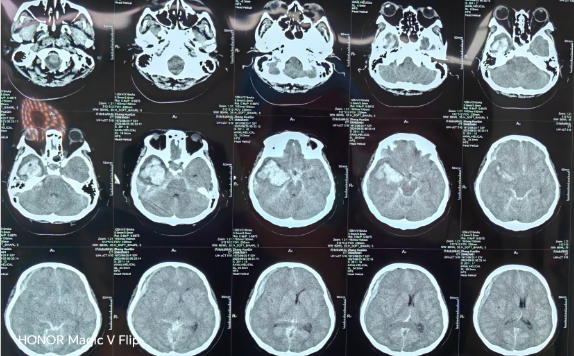

患者被送至济南南郊医院脑病科时,已处于深度昏迷状态,呼吸、心跳等生命体征极不平稳,随时可能停止。检查发现,其脑动脉瘤破裂后出血量巨大,形成的血肿已导致脑组织移位,压迫到维持心跳、呼吸的生命中枢——这是典型的脑疝表现,死亡率极高。

抢救这样的病人,对医疗团队是极大的考验。郭晓宾主任将这场手术比喻为一台“拆雷+排雷”的复合手术:不仅要清除占据空间、压迫大脑的巨大血肿(排雷),还要在视野不清、操作空间极其有限的情况下,精准找到那个随时可能再次破裂的动脉瘤,并成功将其夹闭(拆雷)。整个过程技术要求极高,容不得半点差错。